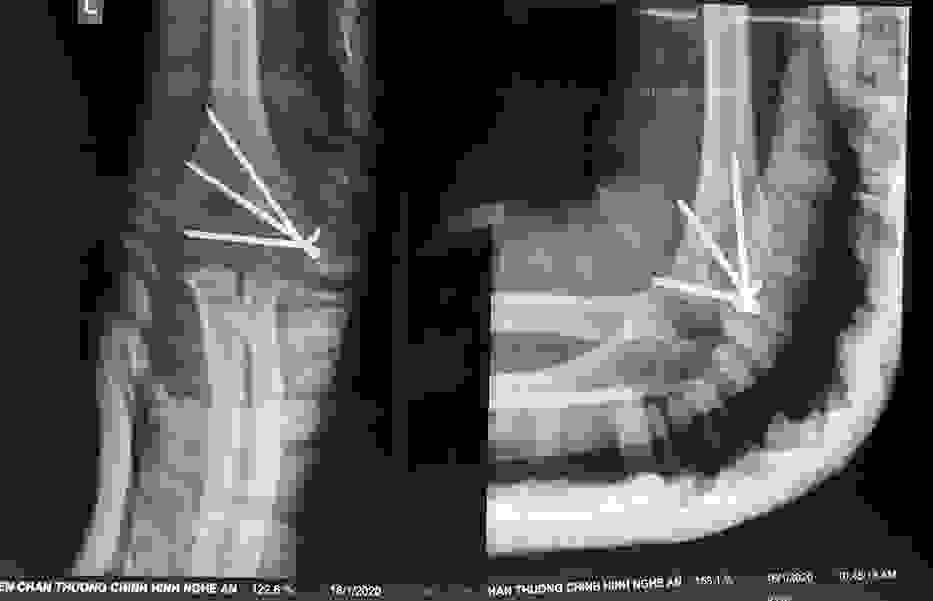

Phẫu thuật thành công ca bệnh hiếm gặp...khớp giả bẩm sinh xương chày

26/06/2019 17:00

Đã xem: 3705

Bệnh viện Chấn thương- Chỉnh hình Nghệ An, vừa phẫu thuật thành công cho bệnh nhi khớp giả bẩm sinh xương chày